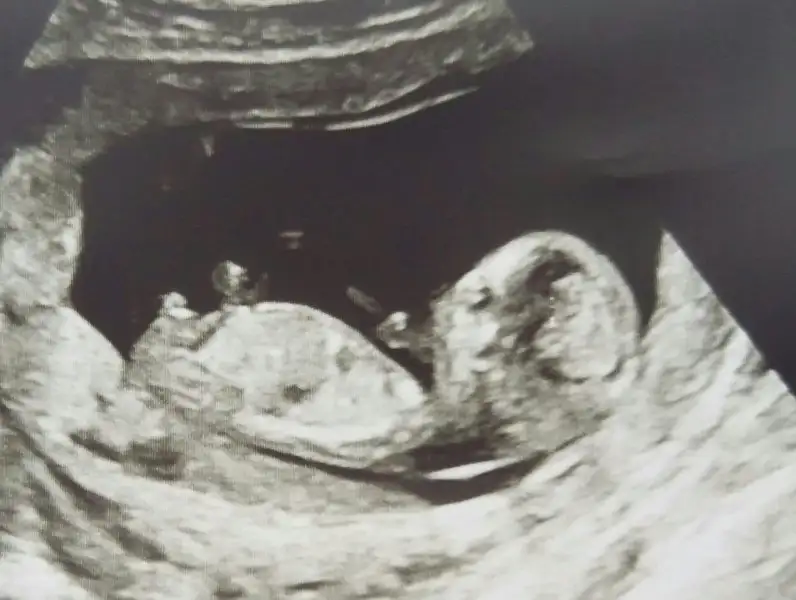

Yaaa maşallah ne tatlı çok net bebiş. Herşeyin yolunda gitmesine çok sevindim. Demek net olarak erkek dedi. Gözünüz aydın. Sağlıkla gelsinlerde. Benimde yarın ikili testim cinsiyetide söyleyecek. Benim bir oğlum var içime doğan yine erkek. Hayırlısı ve sağlıklı olsunlar insallahKizzlar ikili test icin ultrason yaptirdim ve kan verdim. Kan sonucu haftaya ama ultrason gayet iyiydi ense kalinligi 0.80 ve burun kemigi de olusmus Allaha sukur ve cinsiyet icin de erkek dedi doktor cok emin bir sekilde. Bir bakin siz de

Ay maşallah ya nasıl belli gerçektenKizzlar ikili test icin ultrason yaptirdim ve kan verdim. Kan sonucu haftaya ama ultrason gayet iyiydi ense kalinligi 0.80 ve burun kemigi de olusmus Allaha sukur ve cinsiyet icin de erkek dedi doktor cok emin bir sekilde. Bir bakin siz de

ALLAH SAĞLIKLA KUCAGINIZA ALMAYI NASİP ETSİN BEN BU ULTRASON FOTOLARINDNA HİÇ BİŞEY ANLAMIYORUMKizzlar ikili test icin ultrason yaptirdim ve kan verdim. Kan sonucu haftaya ama ultrason gayet iyiydi ense kalinligi 0.80 ve burun kemigi de olusmus Allaha sukur ve cinsiyet icin de erkek dedi doktor cok emin bir sekilde. Bir bakin siz de

Ya bazı ultrasonlar hakikaten çok kaliteli bu da çok net bencede erkek bariz ortada zatenKizzlar ikili test icin ultrason yaptirdim ve kan verdim. Kan sonucu haftaya ama ultrason gayet iyiydi ense kalinligi 0.80 ve burun kemigi de olusmus Allaha sukur ve cinsiyet icin de erkek dedi doktor cok emin bir sekilde. Bir bakin siz de

Gobek bagi daha karina yakin yerden cikiyo. Burda baktigimiz cikinti popoda kuyruk sokumunu. Orda bi cikinti oluyo. Daha erken donemde cikinti bebege dik ve acili ise erkek. Paralel ise kiz diyoruz. Bu ultrason fotografi cok net bazisinda hic gozukmuyoALLAH SAĞLIKLA KUCAGINIZA ALMAYI NASİP ETSİN BEN BU ULTRASON FOTOLARINDNA HİÇ BİŞEY ANLAMIYORUM